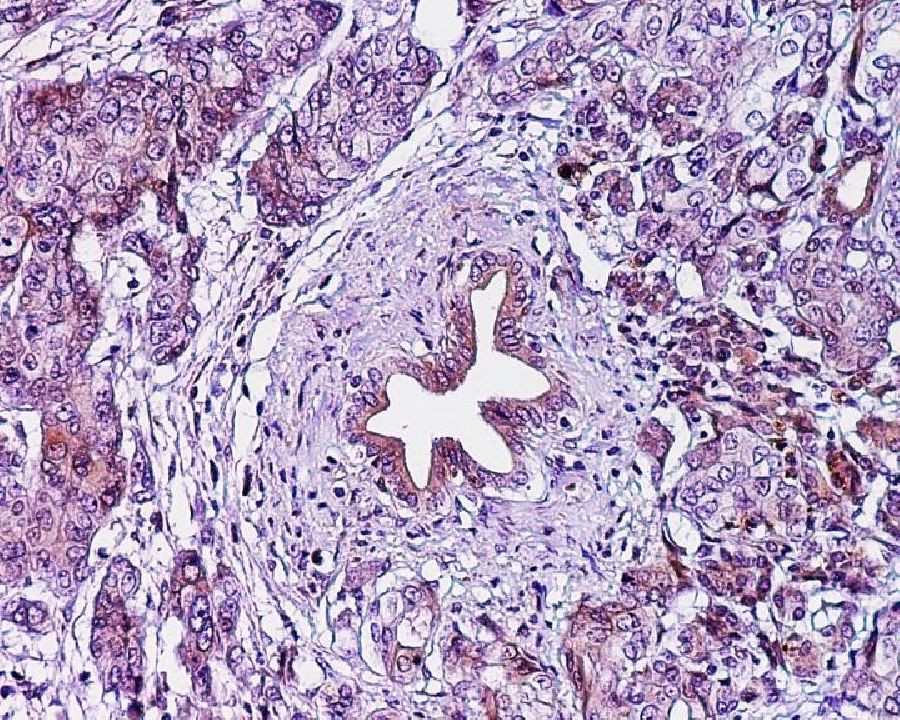

Los investigadores han hecho un llamamiento a los responsables políticos europeos para que destinen los recursos adecuados a la lucha contra el cáncer de páncreas, una enfermedad casi siempre mortal en la que apenas se ha avanzado en los últimos 40 años. Las últimas predicciones sobre las muertes por cáncer en la UE y el Reino Unido para 2021, publicadas en la revista `Annals of Oncology`, muestran que las tasas de mortalidad por cáncer de páncreas se mantendrán aproximadamente estables en los hombres, pero seguirán aumentando en las mujeres de la mayoría de los países de la UE.

El profesor La Vecchia explica que "entre los principales cánceres, el de páncreas es el cuarto más común y sigue siendo el único que no muestra una caída general en las tasas de mortalidad en las últimas tres décadas en Europa en ambos sexos. Es importante que los gobiernos y los responsables políticos proporcionen recursos para la prevención, el diagnóstico precoz y el tratamiento del cáncer de páncreas con el fin de mejorar estas tendencias en un futuro próximo", reclama.